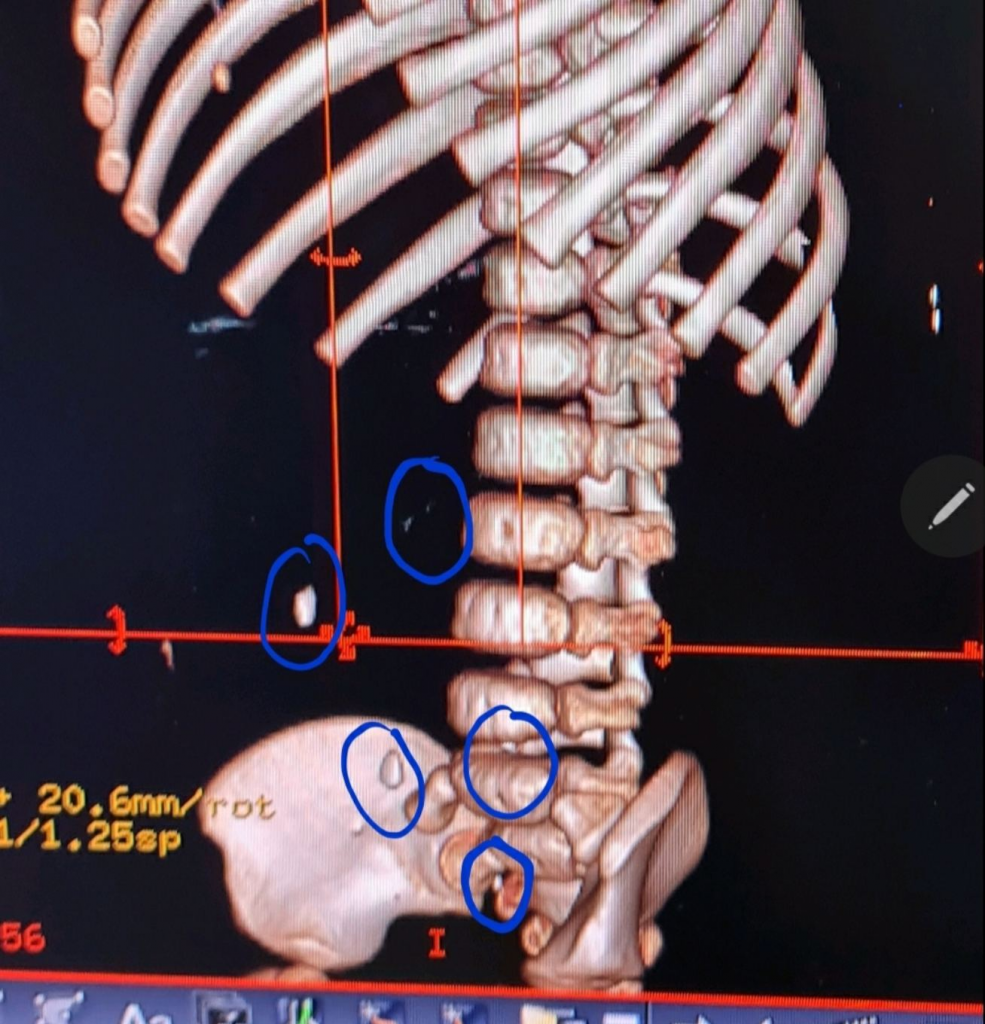

| CT scan ngực bụng cho thấy hình ảnh các mảnh kim loại rải rác |

Tại đây trẻ có biểu hiện khó thở, nhiều đàm nhớt, nôn ói, không bú uống, được hỗ trợ hô hấp thở oxy, chụp X-quang cổ, ngực, bụng phát hiện các mảnh kim loại nằm rải rác trong dạ dày ruột, nên được hội chẩn các chuyên khoa tiêu hóa, hô hấp tai mũi họng, ngoại khoa, chụp thêm CT scan ngực bụng dựng hình thấy rõ các mảnh kim loại rải rác khoảng 5 miếng, di chuyển, nằm rải rác từ ruột non đến ruột già, thật khó khăn cho bác sĩ nội soi gắp dị vật cũng như bác sĩ ngoại khoa khó xác định vị trí dị vật để mổ lấy ra. Sau khi hội chẩn thống nhất ý kiến, chờ đợi 24 giờ với điều trị thuốc xổ uống và bơm hậu môn để trẻ đi tiêu tự nhiên.